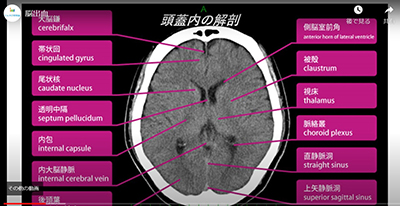

第22回イムスCT研究会をホームページ上で開催しました。今回は、以前から好評であった各講演を動画でオンデマンド配信するという形式で、過去最多となる181名の診療放射線技師が参加しました。今回は『STAT画像報告』に焦点を当て、画像を最初に目にする診療放射線技師として医師に報告すべき内容であり、ガイドラインにも挙がった『脳出血』『脳梗塞』『気胸』『肺塞栓症』『深部静脈血栓症』『大動脈解離』『腹腔内遊離ガス(上腹部)』『腹腔内遊離ガス(下腹部)』の内容をそれぞれ分かり易く解説していました。アンケートでは各内容とも高評価を得ることができました。今後もより実践的で有意義な情報を発信していきたいです。

第20回CT研究会が開催されました。久々のイムス池袋会議室での集合開催とZoomでの同時中継という初の試みでしたが、延べ参加人数は136名と多くの診療放射線技師が参加し、好評を得ることができました。内容は第1部に新規導入経験や教育講演として「80列Aquilion Prime Sp i Editionを導入して」三愛会総合病院 佐々木健司主任、「頭部CT初級編」横浜新都市脳神経外科病院 水浦怜主任、「肝臓の症例検討」新松戸中央総合病院 野澤拓也副主任の3演題が行われました。第2部では第20回記念としてCTクイズ大会を開催し、ハイレベルなクイズと春日部中央総合病院 金子修平主任の軽快な司会で大いに盛り上がりました。今後も参加者が楽しみながらCTについて知識や理解を深められるような内容を提供していきたいです。

IMSグループの診療放射線技師、約100名が参加してCT研究会がZoomで開催されました。基礎講演では川﨑雅弘主任(横浜新都市)が「CT画像活用術」として、迅速な診断や安全な治療につながるSlab MIP画像についてその活用と注意点について解説しました。続いて、「胆道気腫と門脈内ガスについて」(大工原一樹技師・東戸塚)、「病的要因により造影不良になってしまった上肢撮影の一例」(小野里公佑主任・横浜旭)、「泌尿器科領域の救急疾患」(佐々木健司副主任・三愛会)の3症例が報告しました。特別講演は代表幹事の竹之内隆幸技師長(東京葛飾)の進行で、東京都健康長寿医療センター 放射線診療科 鈴木諭貴主任技術員から「実践!CT検査-スキルアップにつなげるために必要な事-」のご講演いただきました。いつでも見られるマニュアルや放射線科情報システムの活用について、装置特性の活用と治療に生かすについて症例の画像を用いてご説明いただきました。

IMSグループ放射線部主催の第15回イムスCT研究会がZoomにて開催しました。初のWEB開催でしたが22施設、132名と過去最多の放射線技師が参加しました。内容は4部構成で第1部「Killer disease(頭部領域)」横浜新都市脳神経外科病院 水浦怜主任、第2部「頭部領域~3D構築の基本と実践~」東戸塚記念病院 佐藤祐太主任の両発表では脳外科領域を中心に血管解剖・症例・オペに役立つ画像構築など、基礎的な知識から若手指導に有用な講義で直ぐ業務に活かせる内容でした。第3部「造影剤漏出の現状 アンケート」は48施設に協力頂きグループ内の造影検査時の対応を把握することができました。第4部「COVID-19の撮影状況と症例」横浜旭中央総合病院 小野里公佑副主任より過酷な現場報告から対応方法・感染防止は非常に参考になる内容でした。今後も意見・要望を取入れ、来年6月開催を予定しています。